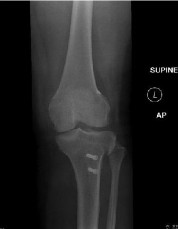

Question 14:

A 23-year-old collegiate basketball player sustains a fracture of the fifth metatarsal at the metaphyseal-diaphyseal junction (Jones fracture). He demands the quickest safe return to play. What is the current standard of care for a competitive athlete with an acute Jones fracture?

Correct Answer: Percutaneous intramedullary screw fixation

Explanation:

Acute Jones fractures (Zone II) in high-level competitive athletes are best treated with intramedullary screw fixation. This approach significantly decreases the time to clinical and radiographic union, decreases the nonunion rate, and allows for a much earlier return to play compared to conservative management.